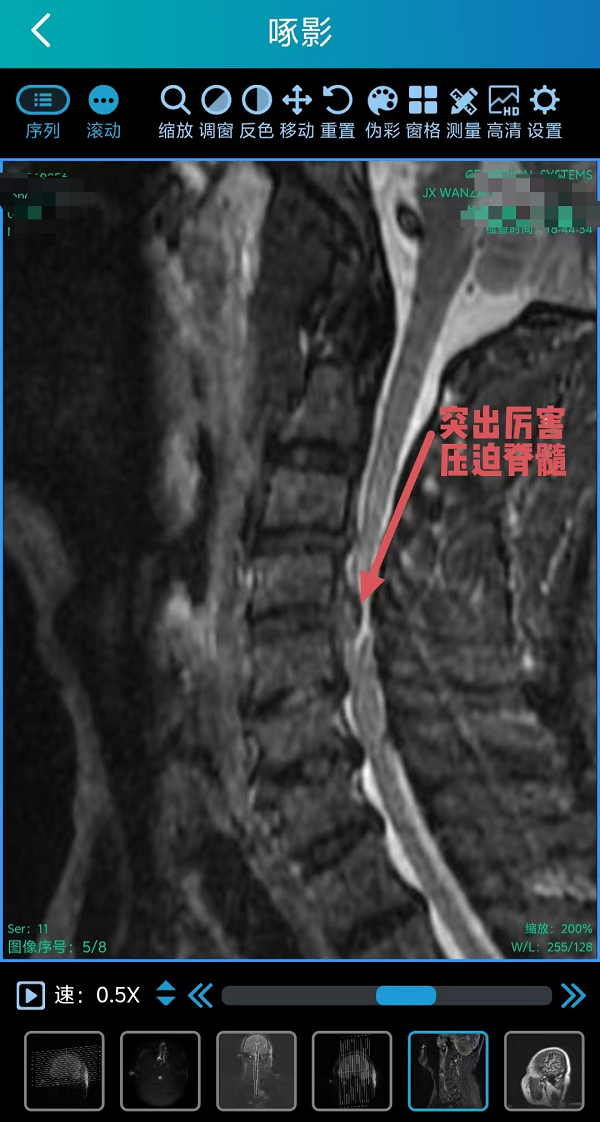

2. 为颈椎间盘巨大突出致肢体不全瘫患者行颈椎前路椎间盘切除融合内固定术(ACDF)(四级手术),该术式通过颈部前方的天然解剖间隙到达病变节段,在彻底解除脊髓和神经根压迫的同时,重建了颈椎的生理曲度和稳定性。手术团队凭借丰富的经验和精细的操作,在方寸之间精准完成了减压、植骨与内固定,有效避免了重要神经血管的损伤。